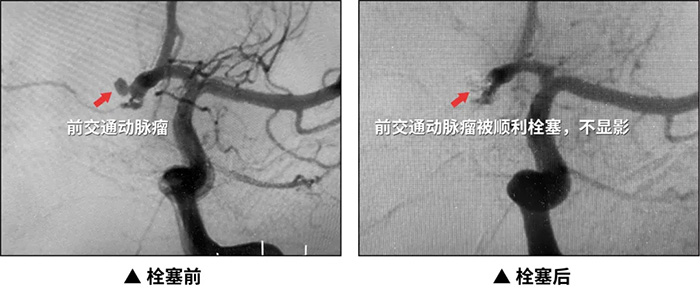

近日,上海蓝十字脑科医院神经外科、脑血管病科、麻醉科团队及导管室介入团队密切配合顺利抢救了一位酒后动脉瘤破裂危在旦夕的患者,并成功行动脉瘤栓塞治疗,患者最终脱离危险,转危为安。

对于破裂性颅内动脉瘤,一旦确诊就应急诊处理,患者家属一定要第一时间拨打120,并且要就近去设有卒中中心且有救治能力的医院就诊。存在以下情况的患者建议积极手术:直径≥5毫米的动脉瘤、形态不规则、手术治疗预期风险和难度不大;直径<5毫米的动脉瘤,应根据其形态、位置、数量和患者情况等综合判断。存在以下情况的患者推荐积极干预:动脉瘤伴有子囊、多发、位于前交通动脉、后交通动脉和后循环,患者预期寿命>10年,既往有蛛网膜下腔出血病史、有家族史,或需长期口服抗凝、抗血小板药物;随访观察期间,动脉瘤有增大趋势的患者也应考虑干预治疗。